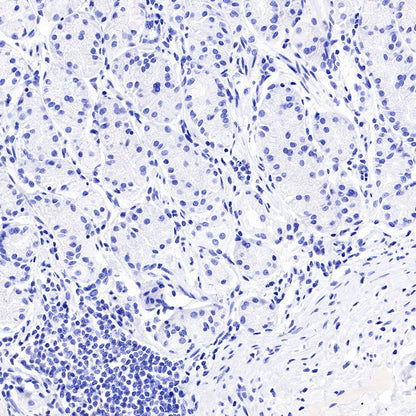

Negative control: IHC shows negative staining in paraffin-embedded human stomach. Anti-PAPP-A antibody was used at 1/1000 dilution, followed by a HRP Polymer for Mouse & Rabbit IgG (ready to use). Counterstained with hematoxylin. Heat mediated antigen retrieval with Tris/EDTA buffer pH9.0 was performed before commencing with IHC staining protocol.